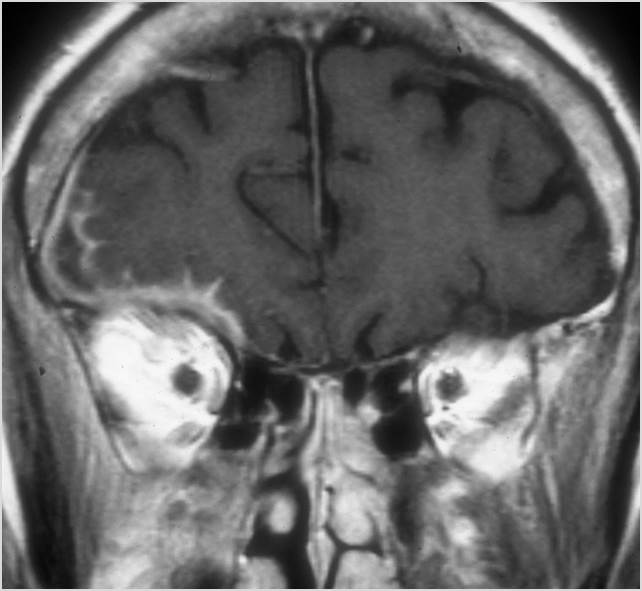

MRI: Anatomically focused axial and coronal images through the temporal bone region and posterior fossa including T1, T2 and diffusion weighted acquisitions done with and without gadolinium contrast enhancement and, when indicated, MRV.

Orbits

The extraocular muscles are swollen or otherwise abnormal. [Yes/No]

The intraconal orbital fat is infiltrated. [Yes/No]

The orbital apex and the superior and inferior orbital fissures are infiltrated. [Yes/No]

The superior and/or inferior ophthalmic veins are dilated or thrombosed. [Yes/No]